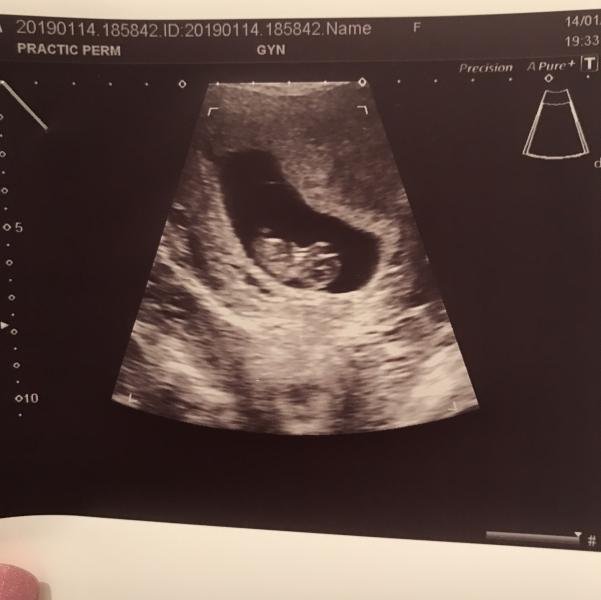

Были вчера с мужем на внеплановом первом УЗИ в МЦ «Практик» на Екатерининской.

Все оказалось хорошо, у нас 9,4 недели. Развиты по срокам, сердцебиение и кровоток👍

Вот такие показатели:

👶🏻 КТР - 26,7 мм

⭐️ Желточный мешочек - 4 мм

🦒Длина шейки - 37 мм

🚫 Отслойки нет, зев закрыт

Врач (Богданова Э.Р.) попалась приятная, все подробно рассказала и показала.